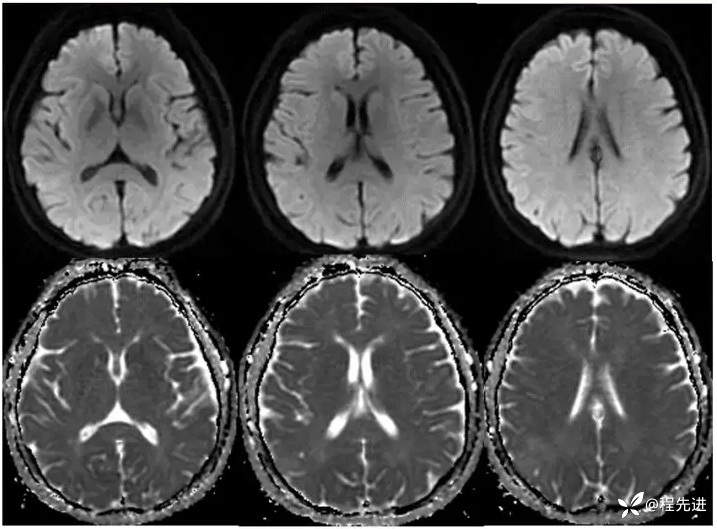

【主诉】:体检发现颅内占位13天

【现病史及既往史】:体检发规颅内占位13天。无恶心呕吐。外院磁共振示,右顶可疑占位,无明显强化。既往史:脑梗塞病史半月余;糖尿病史10余年。

【临床诊断】:颅内占位性病变